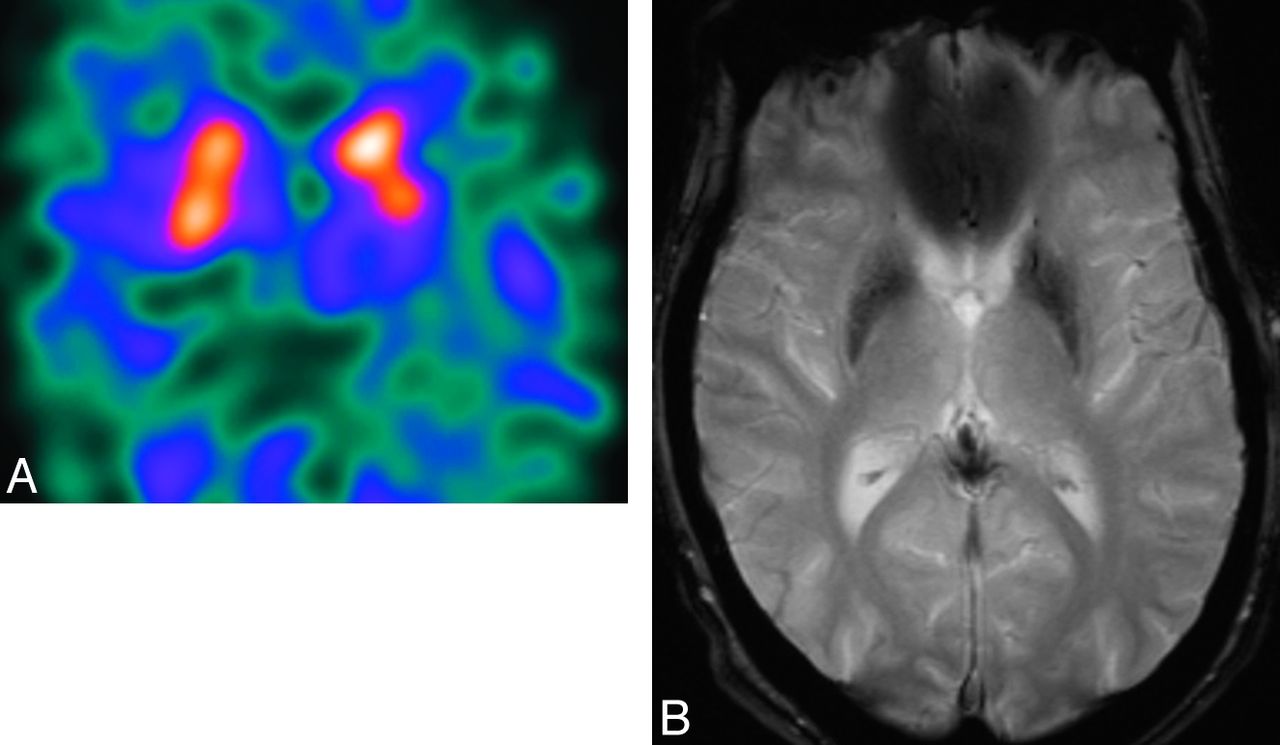

Structural MR imaging findings overlap in all MSA subtypes, independent of clinical presentation, though trends can be seen. In MSA-P, the putamen may demonstrate a rim of increased signal on T2-weighted sequences due to gliosis (Fig 1).5 In MSA with predominant cerebellar ataxia, pontocerebellar degeneration may result in visually apparent cerebellar and pontine atrophy, which, along with MSA-P to a lesser extent, is associated with increased signal on T2-weighted sequences in the middle cerebellar peduncles, cerebellum, and the pontine transverse fibers and raphe (“hot cross bun” sign) (Fig 2).

Axial T2-weighted MR imaging sequence at 1.5T in a patient with MSA-P (A) demonstrating hyperintense putaminal rims. The sign is 96% specific in differentiating patients with MSA from those with idiopathic Parkinson disease; however, it is only 56% sensitive according to 1 study.6 The corresponding coronal T1-weighted MR imaging sequence (B) shows that the putaminal rims are hypointense. The putaminal rim sign is nonspecific in the wider population—for example, it can be seen in Wilson disease or some spinocerebellar ataxia subtypes. It is also a normal finding at 3T.

Axial T2-weighted MR imaging sequence in a patient with MSA with predominant cerebellar ataxia (A) demonstrating the “hot-cross bun” sign, which results from selective loss of myelinated pontine transverse fibers and raphe neurons. One study showed that the sign is 100% specific in differentiating patients with MSA from those with idiopathic Parkinson disease; however, it is only 50% sensitive.6 Marked pontine and cerebellar atrophy is also demonstrated. This olivopontocerebellar volume loss is shown on the sagittal T1-weighted sequences (B), where a middle cerebellar peduncle width <8 mm is demonstrated. All these signs are nonspecific in the wider population—for example, they can be seen in some spinocerebellar ataxia subtypes.

Atrophy is most evident in patients with well-established disease. If one uses a cutoff value of 8 mm, the middle cerebellar peduncle width allows differentiation of patients with MSA compared with controls or those with idiopathic Parkinson disease with 100% positive predictive value (Fig 2).6 Volumetry and voxel-based morphometry group studies show striatal and cerebellar volume loss in patients with MSA-P compared with those with idiopathic Parkinson disease and controls.7⇓–9 Voxel-based morphometry also demonstrates selective cortical atrophy in MSA-P, affecting the motor cortical targets of basal ganglia output pathways such as the primary sensorimotor and lateral premotor cortices and the prefrontal and insular cortices.8